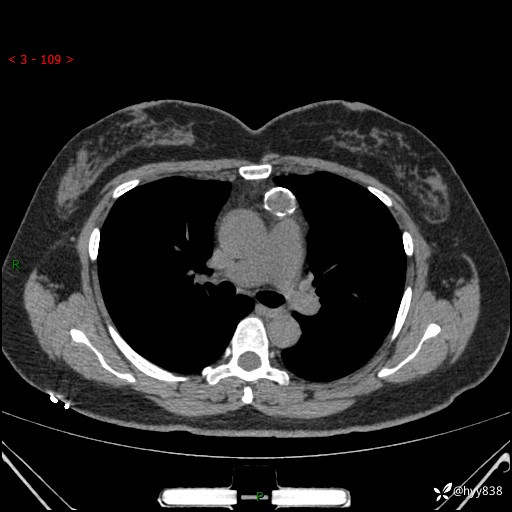

中年女性,检查发现纵隔占位3月余。圆圆的肿物,周围环绕一圈钙化---结果公布~

主诉:检查发现纵隔占位3月余。

现病史:患者于3月前体检行胸部CT检查发现纵隔占位,患者平素无明显咳嗽咳痰,无心慌、胸闷、胸痛、呼吸困难、低热、盗汗,无头痛、头晕,无腹痛、腹胀等不适。现患者欲求进一步治疗,遂来我院就诊,以“纵隔占位”收入我科。 患者自起病以来,精神可,睡眠可,饮食可,大小便正常,体重无明显改变。

胸部CT平扫+增强